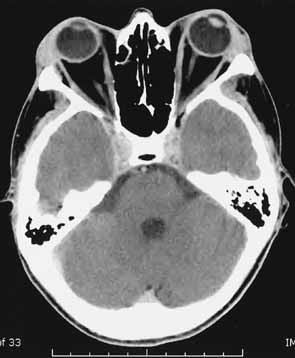

Most cases of optic neuropathy are due to compression of the optic nerve by the enlarged extraocular muscles at the orbital apex (Fig. 5). Patients with compressive optic neuropathy have a more symmetric involvement of the extraocular muscles as compared with most patients with thyroid disease.65 Although patients with optic neuropathy usually have proptosis, optic neuropathy can occur without significant proptosis in patients whose orbital septum efficiently limits anterior globe displacement, despite increased retrobulbar pressure. Very rarely, optic neuropathy can occur without significant muscle enlargement. In these cases, it is postulated that a short optic nerve is being stretched or the optic nerve is being compressed by surrounding orbital fat.49 These cases are so rare that optic neuropathy in the absence of muscle enlargement or proptosis should be investigated thoroughly to rule out other etiologies.

Fig. 5 A. Axial CT scan of a patient with compressive optic neuropathy. Note that position of globe shows only mild proptosis, and orbital fat is not increased in volume. The posterior portion of the extraocular muscles is markedly enlarged, compressing the optic nerve. B. Coronal CT scan of the orbital apex in the same patient clearly shows displacement of orbital fat by enlarged muscles. The apex is “crowded,” consistent with clinical findings of optic neuropathy.